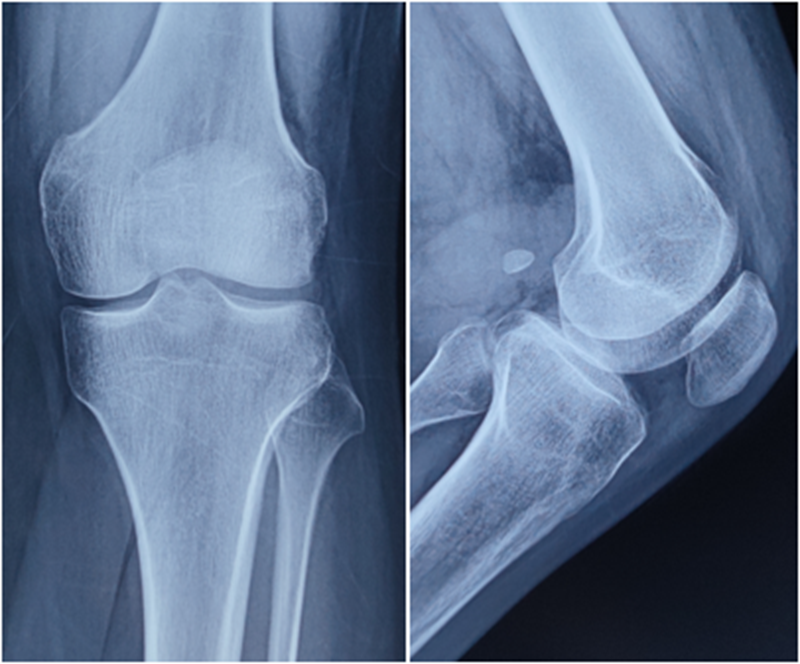

术前X线

术后X线